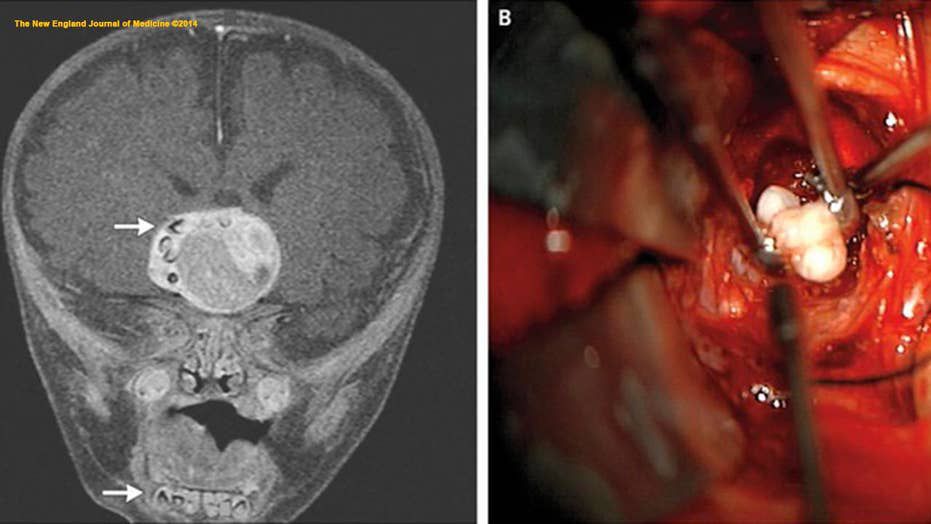

A unusual sort of brain tumour caused teeth to develop in the brain of an infant in Maryland. According to a report published in the New England Journal of Medicine in February 2014, doctors were able to remove the tumour and the boy recovered completely. When the boy's skull appeared to expand faster than usual for his age, doctors thought something was wrong inside his brain. A brain scan revealed a tumour containing what seemed to be teeth ordinarily located in the lower jaw. Indeed, when the tumour was removed, several completely grown teeth were extracted as well. While teeth have been seen in tumours before, the sort of tumour taken from the infant's brain — a craniopharyngioma — was not known to contain these unusual features. via LiveScience.